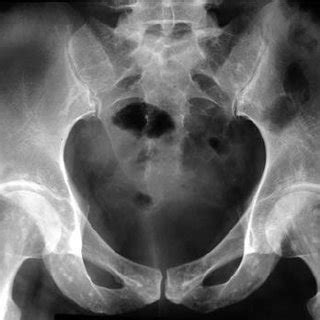

Overlap syndrome in a 25- year-old man. Pelvic radiograph ...

Overlap syndrome in a 25- year-old man. Pelvic radiograph ... from www.researchgate.net

Osteopathia striata features linear striations at the ends of long bones and in the ileum,25 and is a curiosity when the skeletal findings occur alone as an autosomal dominant trait. Male child with somatic mosaic osteopathia striata with cranial sclerosis caused by a novel pathogenic amer1 frameshift mutation. Typically, osteopathia striata is diagnosed based on its characteristic findings on imaging. The mother had two previous pregnancies in which the male fetus had multiple anomalies. Osteopathia striata is an asymptomatic disease, usually discovered accidentally during a radiological survey for other reasons.

Clinical, genetic and radiologic considerations. Osteopathia striata with cranial sclerosis (oscs; A case of osteopathia striata, childhood cataracts, short stature, elbow deformity, and microdontia with rhizomicry in a white male is reported. Osteopathia striata is an uncommon sclerosing bone dysplasia that remains mostly asymptomatic. Osteopathia striata associated with familial dermopathy and white forelock: Description, causes and risk factors: Osteopathia striata is an asymptomatic disease, usually discovered accidentally during a radiological survey for other reasons. It is often asymptomatic, and is often discovered incidentally. Osteopathia striata, also known as voorhoeve's disease, is a benign autosomal dominant or sporadically inherited disorder in bone formation first described by voorhoeve in 1924. Multiple condensations of cancellous bone beginning at the epiphyseal line and extending into the diaphysis, an abnormality seen only on radiographic examination. Osteopathia striata features linear striations at the ends of long bones and in the ileum,25 and is a curiosity when the skeletal findings occur alone as an autosomal dominant trait. Here, we report a case of osteopathia striata with cranial sclerosis in a male baby. Osteopathia striata, also known as voorhoeve disease, is a rare, benign sclerosing bone dysplasia, involving the epiphysis and metaphysis of tubular bones.